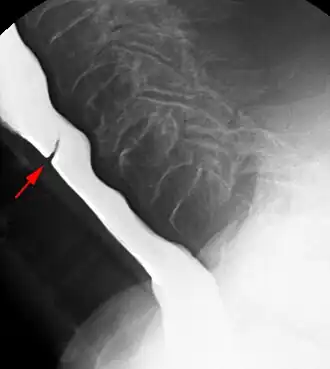

Esophageal webs are thin 2–3 mm (0.08–0.12 in) membranes of normal esophageal tissue consisting of mucosa and submucosa that can partially protrude/obstruct the esophagus. They can be congenital or acquired. Congenital webs commonly appear in the middle and inferior third of the esophagus, and they are more likely to be circumferential with a central or eccentric orifice. Acquired webs are much more common than congenital webs and typically appear in the cervical area (postcricoid).

The diagnostic test of choice is a barium swallow.